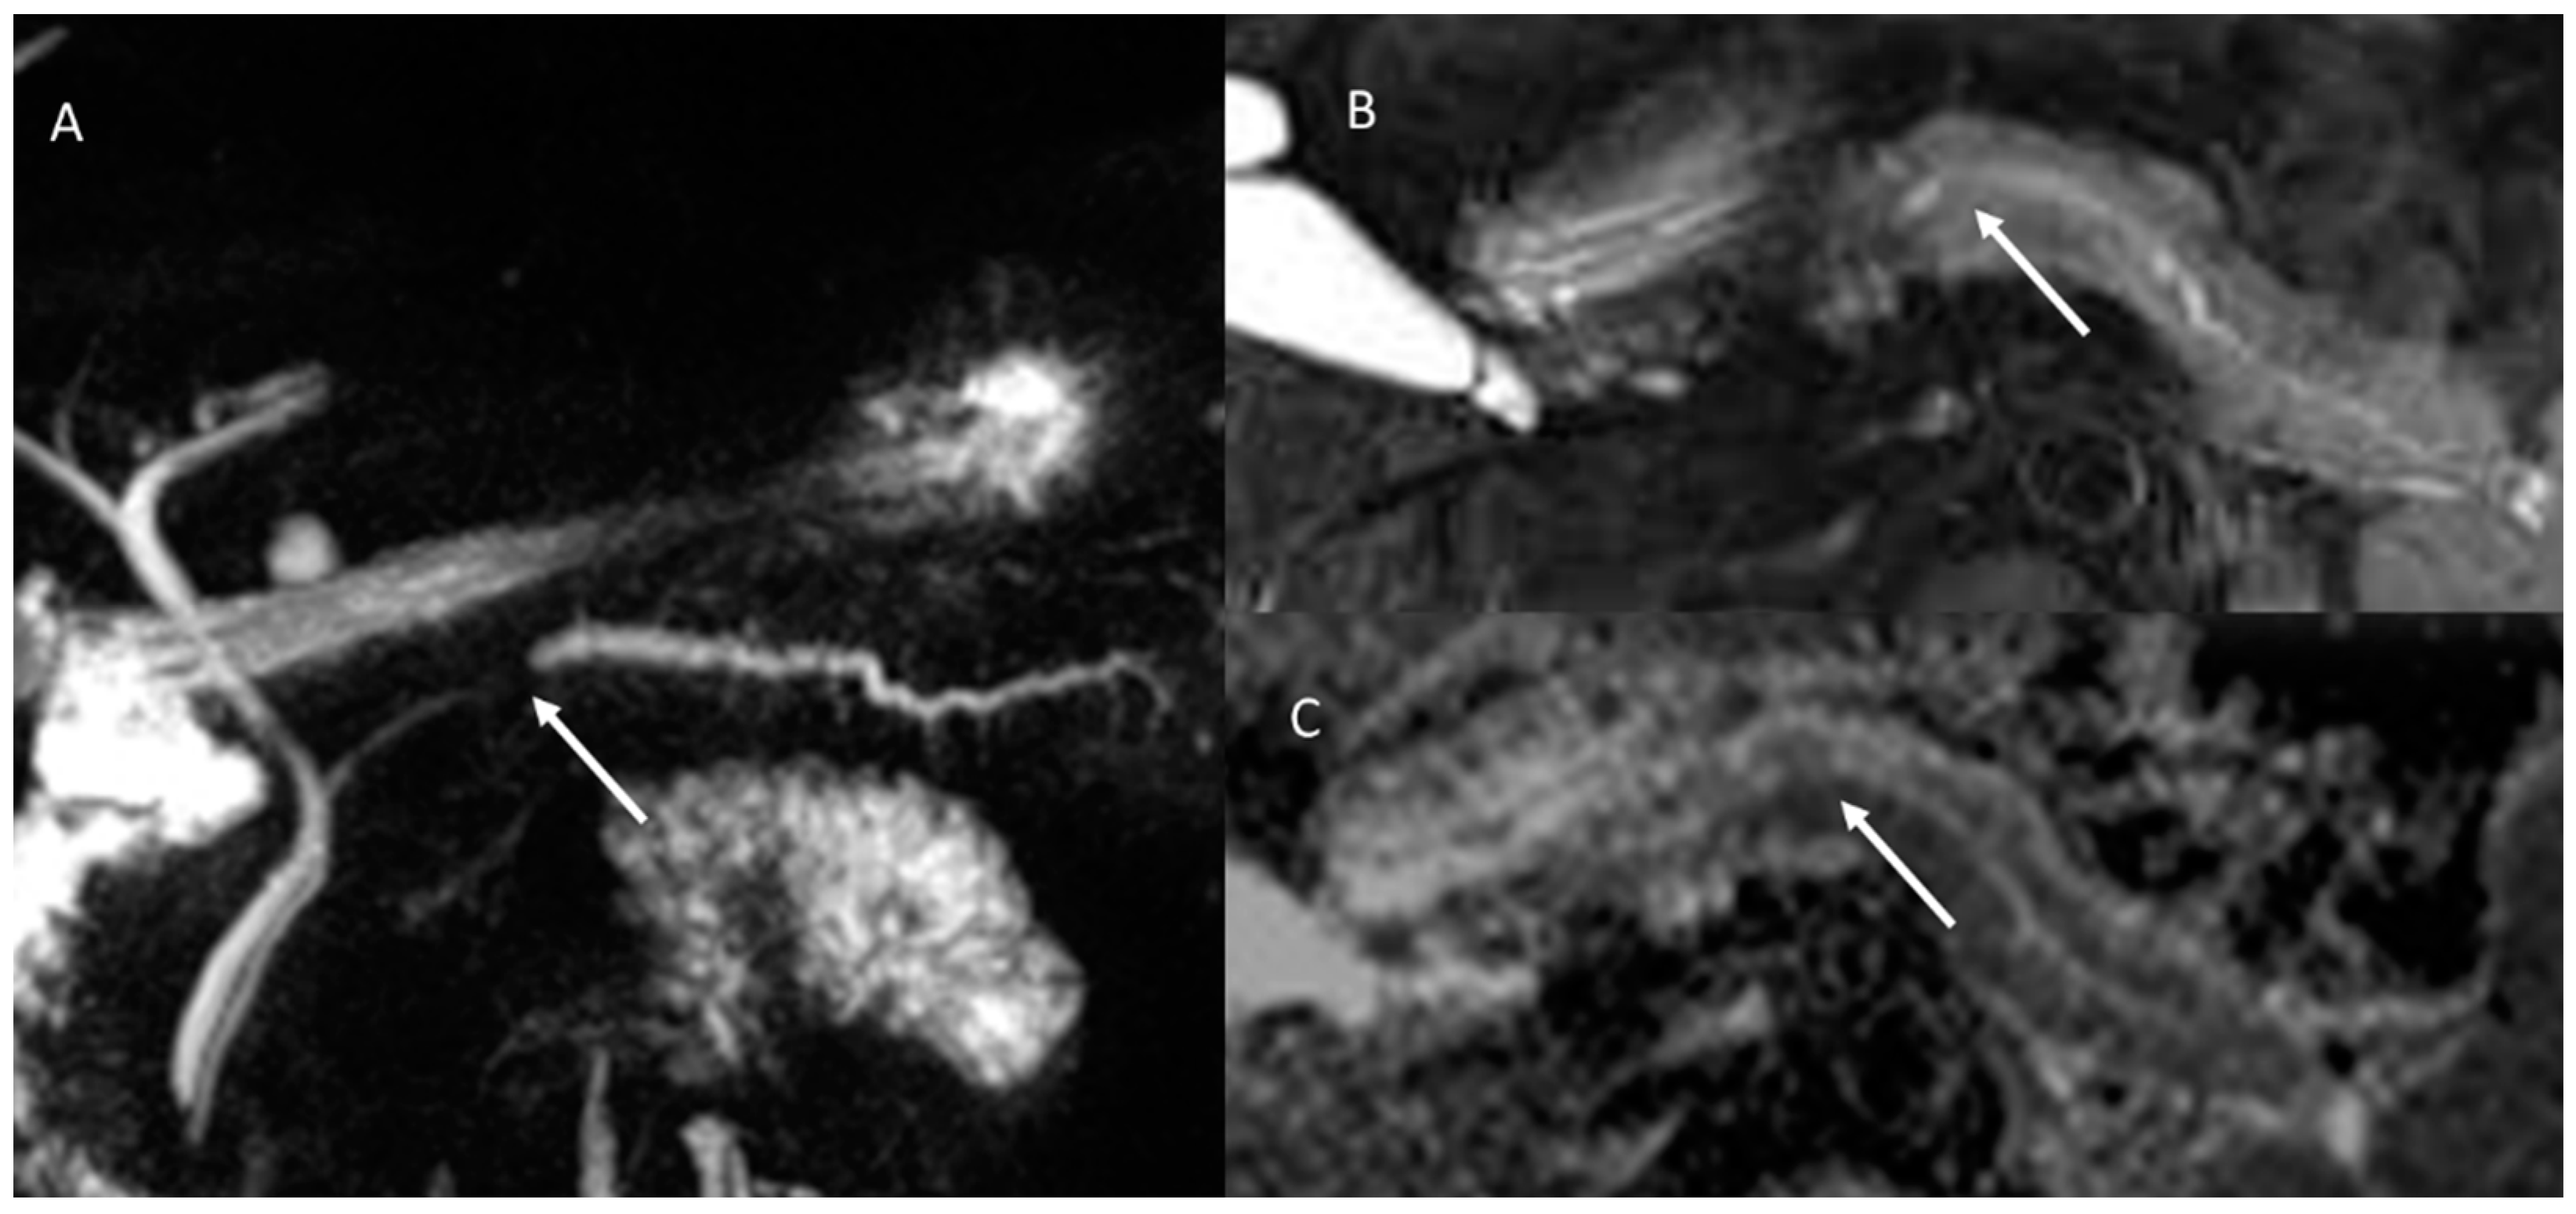

- Granata, V.; Fusco, R.; Sansone, M.; Grassi, R.; Maio, F.; Palaia, R.; Tatangelo, F.; Botti, G.; Grimm, R.; Curley, S.; et al. Magnetic resonance imaging in the assessment of pancreatic cancer with quantitative parameter extraction by means of dynamic contrast-enhanced magnetic resonance imaging, diffusion kurtosis imaging and intravoxel incoherent motion diffusion-weighted imaging. Ther. Adv. Gastroenterol. 2020, 13, 1756284819885052. [Google Scholar] [CrossRef]

- Granata, V.; Grassi, R.; Fusco, R.; Galdiero, R.; Setola, S.V.; Palaia, R.; Belli, A.; Silvestro, L.; Cozzi, D.; Brunese, L.; et al. Pancreatic cancer detection and characterization: State of the art and radiomics. Eur. Rev. Med. Pharmacol. Sci. 2021, 25, 3684–3699. [Google Scholar] [CrossRef] [PubMed]